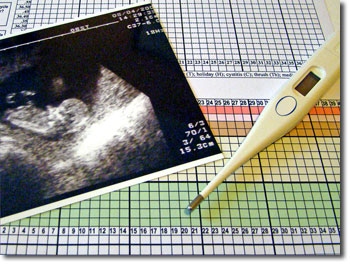

Diagram of female fertile cycleThe women takes her temperature each morning, on waking, and records the information on a chart. A sustained temperature rise indicates that ovulation has taken place in that cycle, and helps define the end of the fertile phase. The temperature rise alone will not help a couple to achieve a pregnancy as it is now ‘too late’ for that cycle. The ovum lives for up to 12 hours. However the sperm can live for up to six days in optimum conditions, which occur before ovulation.

NFP ChartAfter all, if we were created by a loving God, surely He would have taken into account our ability to procreate. The discovery and understanding of natural fertility, has been a long and at times painful and discouraging journey. We are now benefiting from previous research, and NFP has become more accepted in the last few decades.